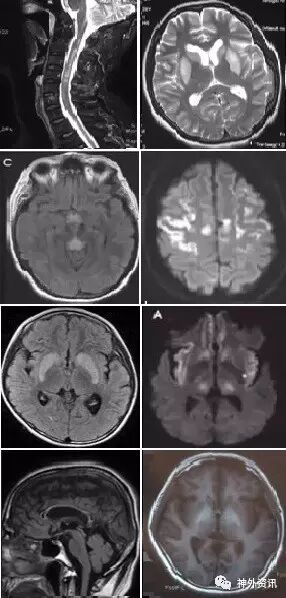

(重要申明:以下每个部分会配磁共振图片,因疾病和影像之间存在同病异象、同像异病,为避免误导,图片不标注疾病,其各自鉴赏,另其中的部分图片来源于网络,有疑问可与本人联系)

引起中枢神经系统病变的遗传性疾病可是种类繁多,主要指脑白质营养不良、脑小血管病等白质受累为主的病变。

如前者按发病机制可分为:溶酶体疾病(异染性脑白质营养不良、Fabry’s 病、Krabbe’s 病),过氧化物酶疾病(肾上腺脑白质营养不良(ALD)、肾上腺脊髓神经病(Adrenomyeloneuropathy))、线粒体疾病(MELAS、Leigh病)。按髓鞘病变病理过程种类分:异常髓鞘化:肾上腺脑白质营养不良、球形细胞脑白质营养不良、 染性脑白质营养不良;髓鞘化低下:佩梅氏病、Alexander病、白质消融性脑白质病;髓鞘囊性变性:Canavan病、空泡性脑白质病。

各种遗传性脑小血管病:如CADASIL、CARASIL、Fabry病及CAA、CAA相关性血管炎等等。

还有结节性硬化、各类NBIA(脑组织铁沉积神经变性病),脑肝肾综合征、线粒体脑病、LCC等。

各种中毒,有机溶剂,如苯、甲醇、一氧化碳中毒、氨己烯酸中毒等。

毒品如海洛因、可卡因等。

抗肿瘤或免疫抑制剂如甲硝唑、5-FU(5-氟尿嘧啶)及其前体药物卡培他滨、他克莫司、甲氨蝶呤、贝伐单抗等相关性脑病。